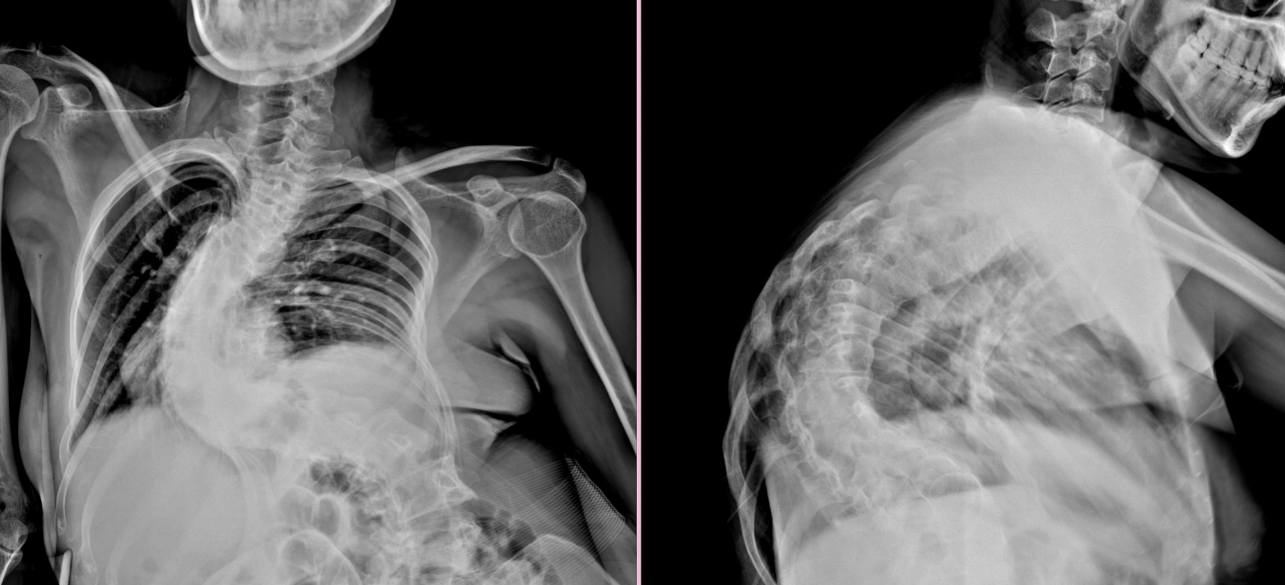

Phim chụp cột sống của bệnh nhân